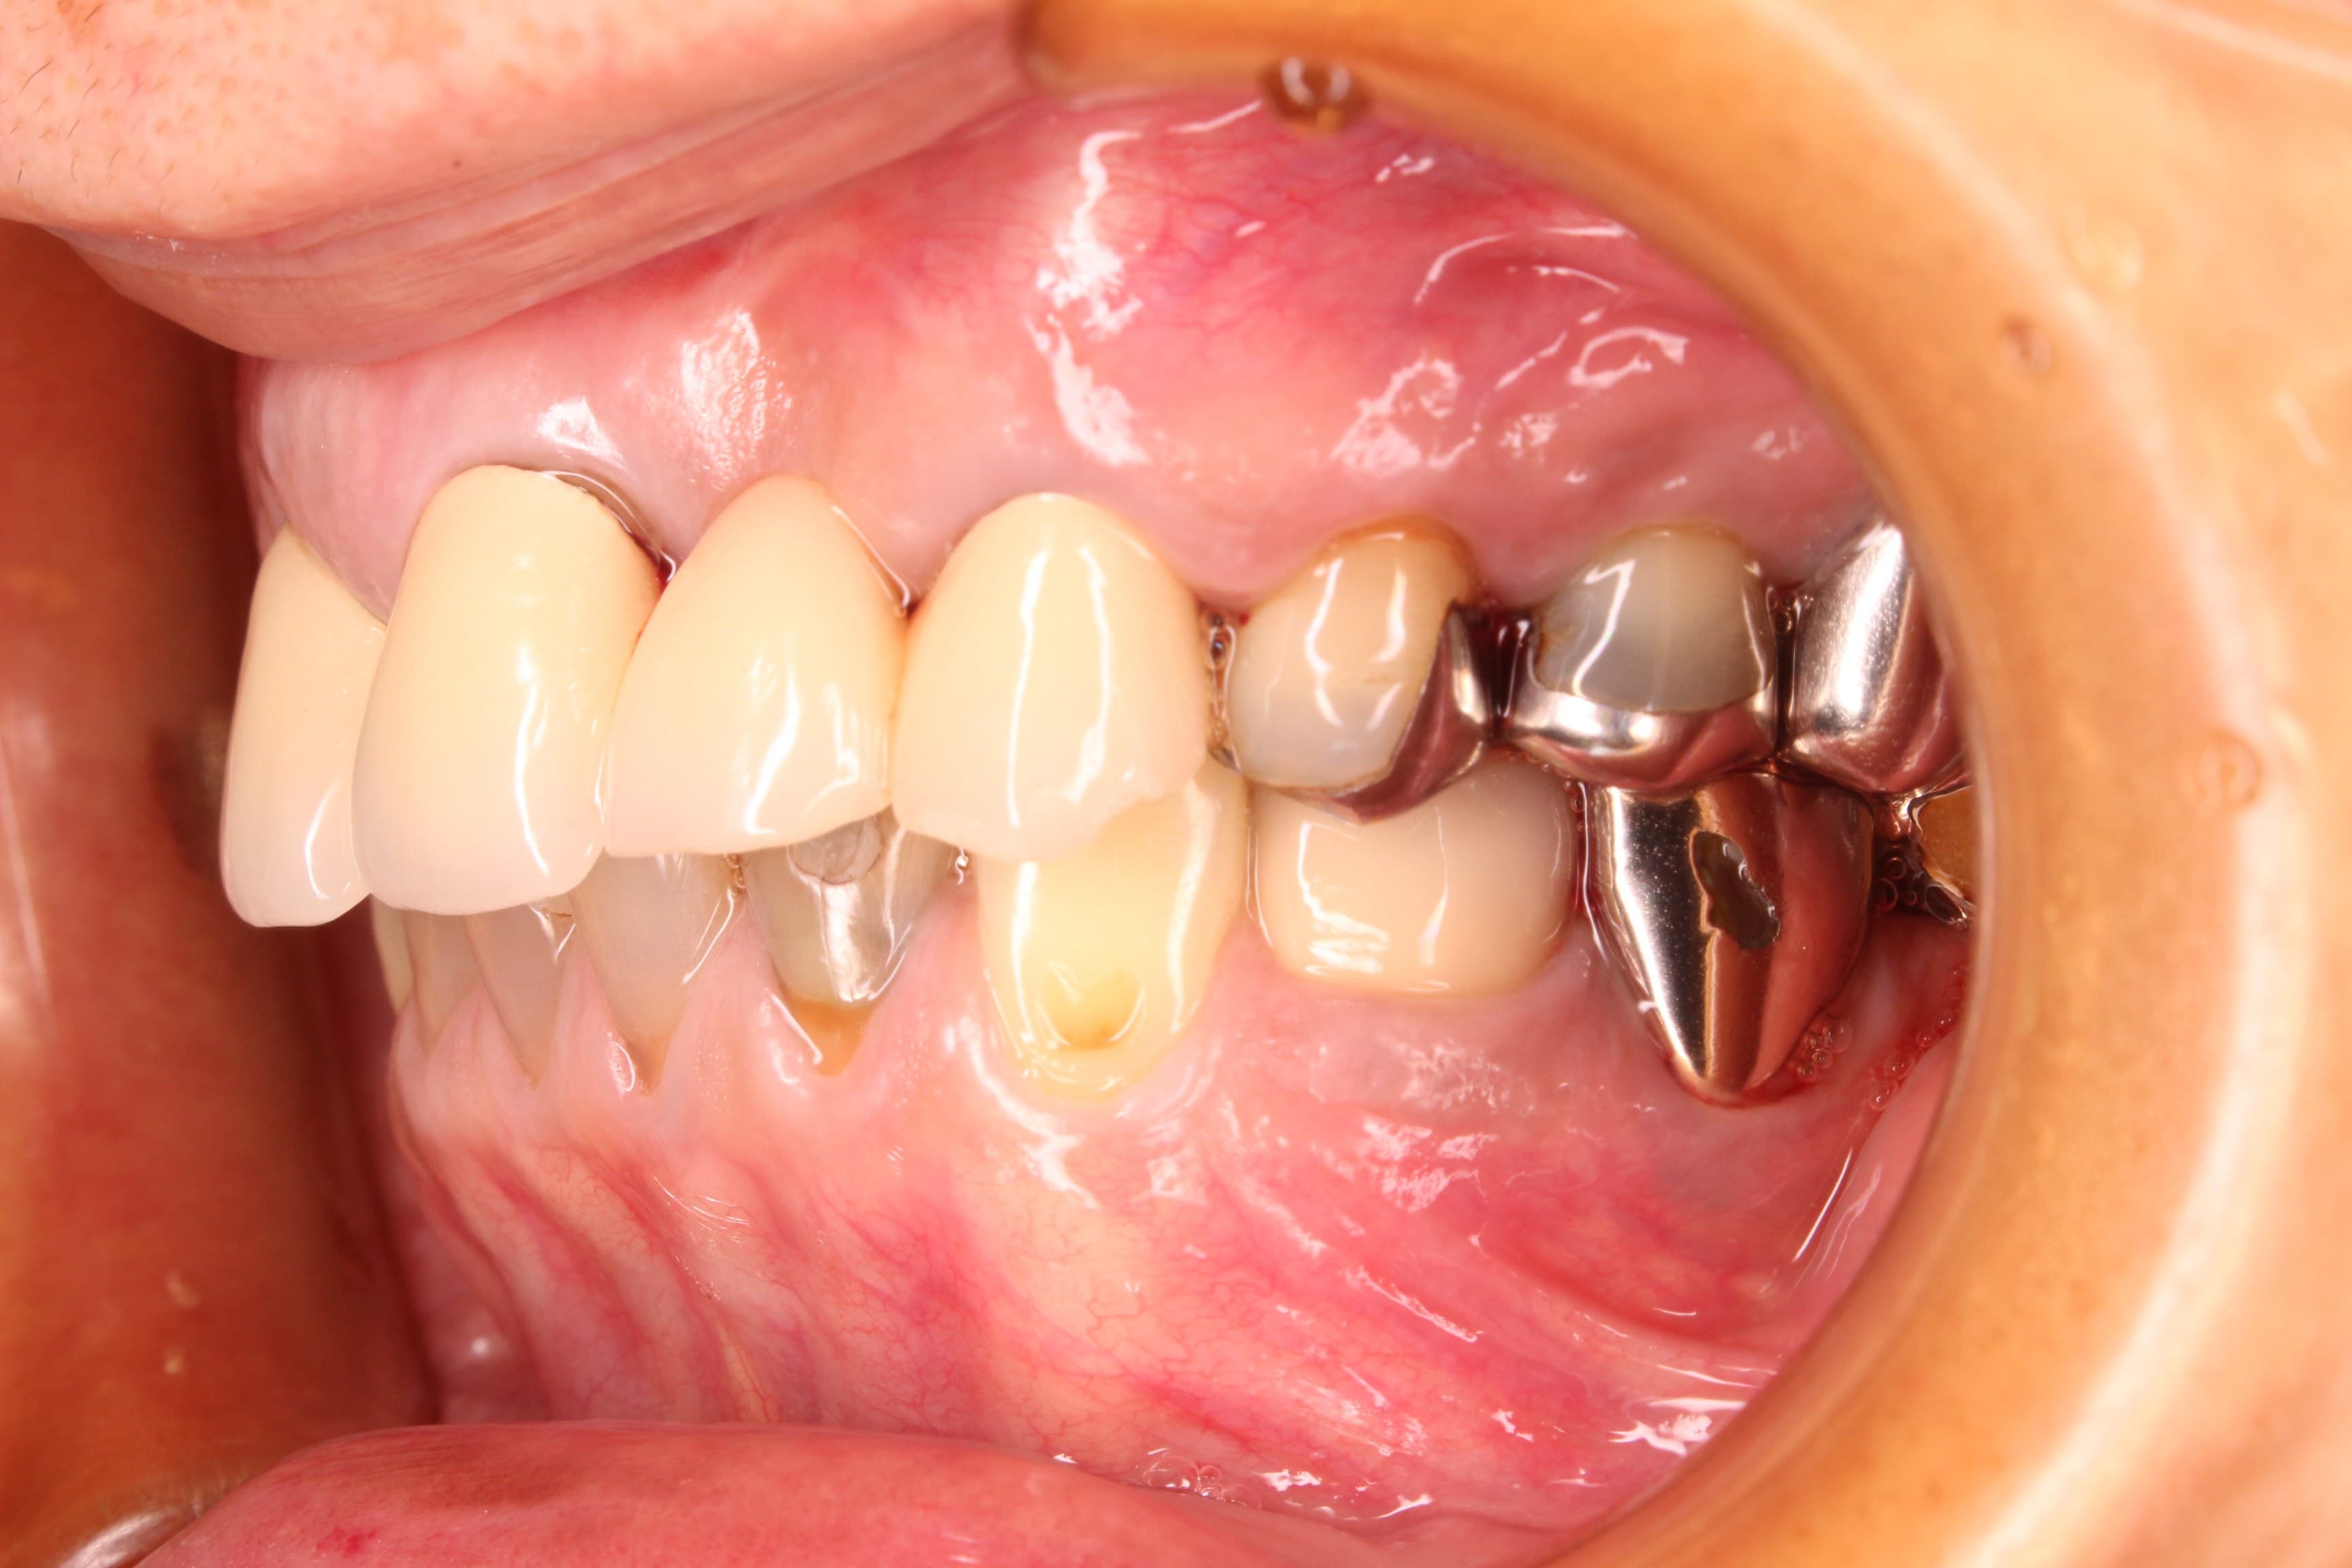

治療前

土台に使用していた歯の状態と、噛み合わにも問題があったのですが、非常に出血が多く、先ずは歯周病を改善する必要がありました。